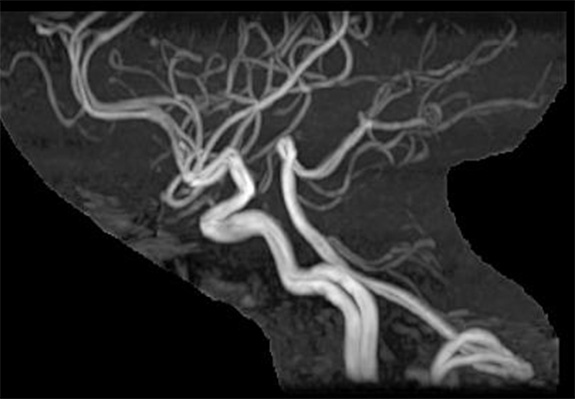

頭の中の動脈の血管です。

横回転で12方向、縦回転で12方向の計24方向の頭部動脈の写真を作りいろいろな角度から観察します。この写真は横回転、縦回転の中の一枚ずつの写真です。

この画像で血管の途中が狭くなっていたり無くなっていないかを見たり、未破裂動脈瘤と言って血管にコブみたいなものが出来ていないか確認することができます。

血管狭窄(頭部血管)